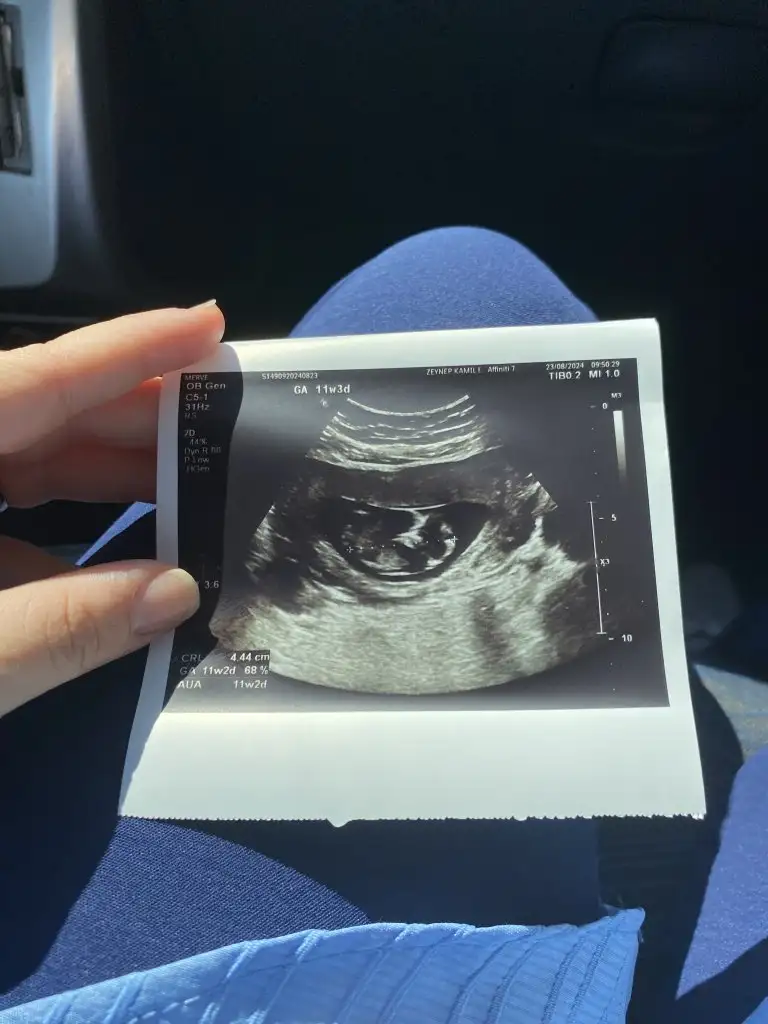

Kızlar 14+3 cinsiyet tahmini alabilir miyim sizden ricam tesekkur ederim 🙏